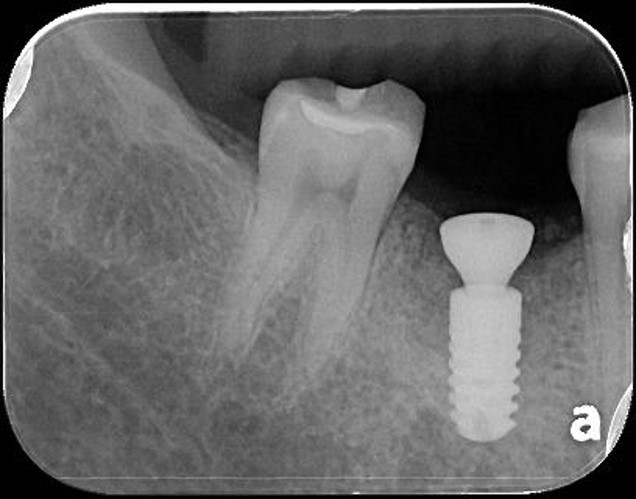

治療前,牙齒長膿胞

治療前,牙骨已破壞

6個月後,骨癒合